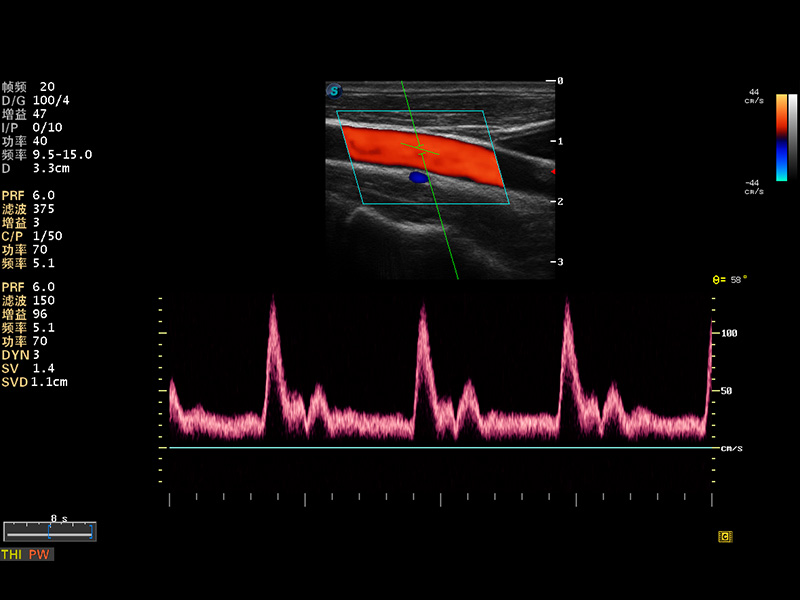

S8 EXP便携式彩色多普勒超声诊断仪是银河集团官网研发的高端全身应用型便携彩超。高通道的VIS平台融合可视化(Visual)、智能化(Intelligent)和人性化(Smart)的特点,配以银河集团官网自主研发生产的探头大家族,使您能够快速、准确的获得病人信息,提高工作效率的同时减轻疲劳。

多波束形成器

μ-Scan微米成像